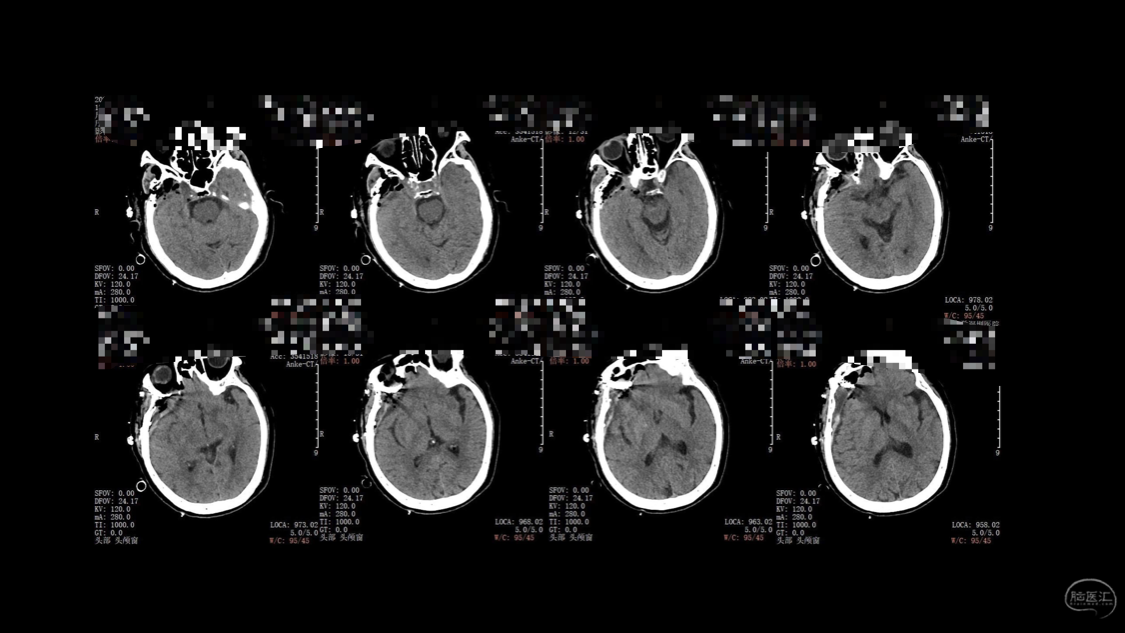

陈保东教授手术作品-右眶内及海绵窦旁孤立性纤维瘤